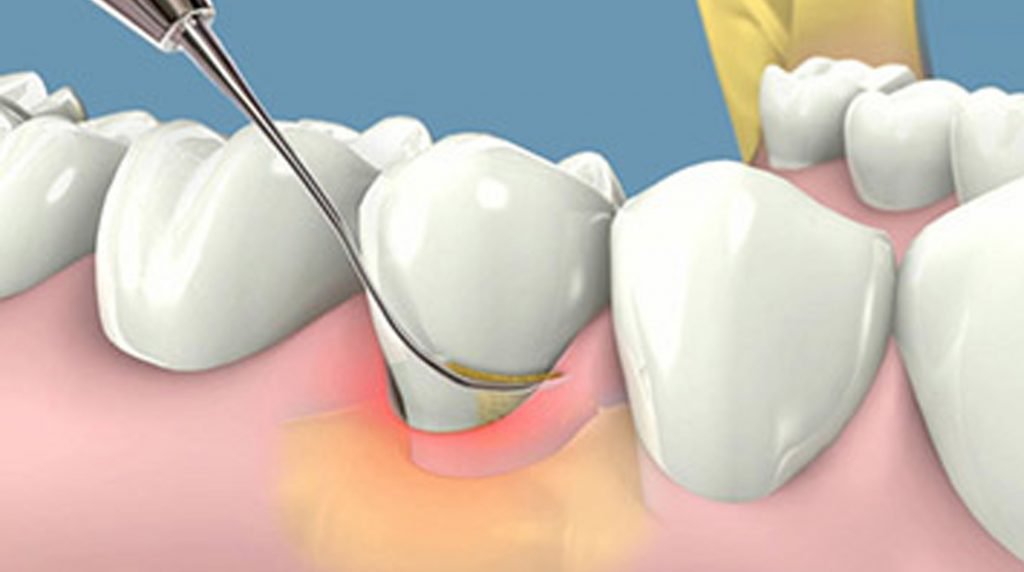

Hình ảnh lấy vôi răng

Đối với những ca răng nhạy cảm hoặc có mảng bám cao răng dày có thể gây ra tình trạng ê buốt và chảy máu chân răng nhẹ. Nhưng đừng quá lo lắng, tình trạng này sẽ hết sau 12-36 giờ mà không cần sử dụng thuốc.